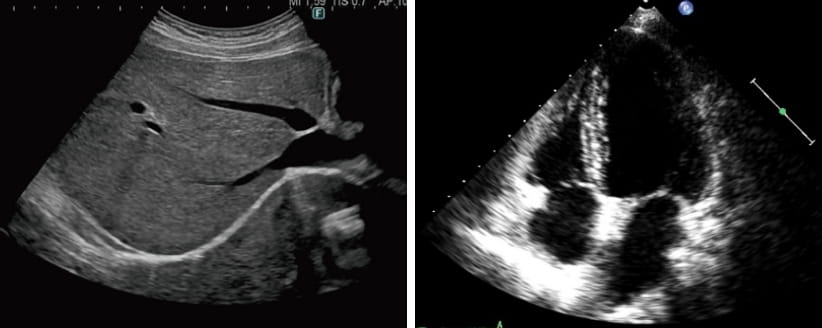

体の表面にゼリーを塗り、超音波を当てて内部をモニターに映し出します。

心臓の形や動き、お腹の臓器(肝臓・腎臓など)、血管の詰まりなどが詳しく分かります。

研修医や地域の医師や臨床検査技師、診療放射線技師を対象に、超音波検査を中心とした教育・研修を行っています。

部位ごとに明確な目標を設定し、マニュアルに基づいた指導と評価を実施しています。